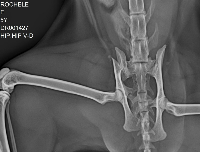

Ela sofreu um acidente ainda desconhecido, mas muito provavelmente ela foi atropelada. Ela tem 2 fraturas na pelve e escoriações pelo corpo. Vai precisar de cirurgia para estabilizar e no momento eu não tenho condições 😭😭